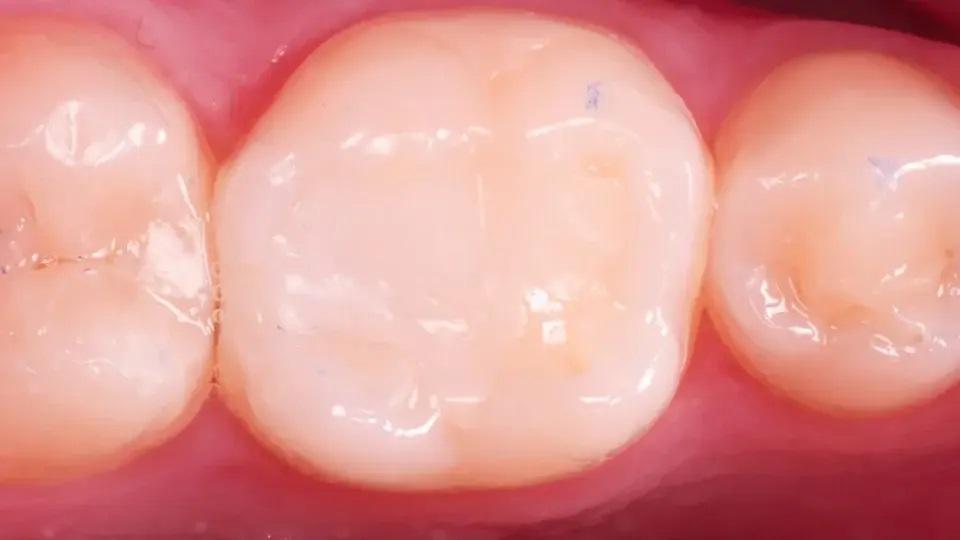

После примерки (фото 22), реставрация была выполнена с использованием плотного композита сверхнизкой текучести Estelite Universal Flow (SuperLow) (фото 23). Лишний материал был удален (фото 24), затем последовал еще один этап легкой полимеризации в течение 20 секунд с каждой стороны. Было произведено окончательное удаление излишков (фото 25), а благодаря предварительно сформированной анатомии большая часть морфологических деталей осталась нетронутой даже после окклюзионной коррекции (фото 26). Была сделана контрольная рентгенограмма (фото 27).

Фото 26: Окклюзионный вид после окончательной коррекции.